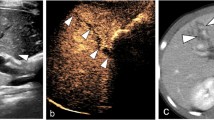

Spleen is the most frequently encountered organ injury in blunt abdominal trauma patients. Most splenic injuries can be treated conservatively, in the absence of absolute clinical indication for surgery at admission. However, delayed failure of nonsurgical treatment (bleeding) has been formerly reported in 10–31% of cases [8] and may occur up to 10 days (or even later) after trauma. A major improvement in the non-operative management of blunt splenic trauma patients was achieved when two major observations were reported in the scientific literature. Firstly, an association was established between the presence of intrasplenic vascular injuries at CT and an increased risk of delayed bleeding [9]. Secondly, the angiographic embolization of these vascular injuries has been associated with a significant drop in the rate of unsuccessful non-operative management (from 13% to 6%) [10]. Based on these observations, the classical AAST-1994 surgical splenic injury scale classification, only based on morphological criteria, was completed by a CT-based classification initially proposed by Stuart Mirvis [11] and slightly reshuffled in 2018 [12]. This classification takes into account vascular lesions (pseudoaneurysms, arteriovenous fistula or active bleedings) confined within the spleen (Fig. 1.1) and those extending beyond the spleen (active bleeding). Vascular splenic lesions appear at CT as focal blush of contrast with an attenuation close to arteries and greater than that of the spleen parenchyma. Delayed CT images must be systematically obtained in the presence of a vascular lesion to differentiate those that vanishes (pseudoaneurysms and arteriovenous fistula) from those which stay and expand (active bleeding).

Whether a systematic follow-up imaging patients should be performed in hemodynamically stable blunt splenic trauma patients remains a yet unsolved question. It has been reported that a majority of traumatic splenic pseudoaneuryms (38%–74%) would only be detected on control CT performed within 24–72 h after admission [13]. For practical reasons, most of the trauma associations do not recommend a systematic delayed CT in hemodynamically stable splenic trauma patients. With a reported 75% sensitivity and 100% specificity for detection of delayed splenic pseudoaneurysms (in skilled hands), bedside contrast enhanced sonographic examination has been advocated as a good option in this setting [14].

The diagnosis of acute cholecystitis may be more difficult in patients with superimposed chronic cholecystitis, in which case the gallbladder may be contracted rather than distended. Gangrenous cholecystitis may present with intramural gas and potentially a lack of Murphy’s sign. As it may lead to perforation, an early diagnosis is important and is suggested by the presence of mucosal defects or frank wall discontinuity (Fig. 1.7). Xanthogranulomatous variant of cholecystitis can be difficult to differentiate from gallbladder cancer but is suggested by the presence of lipid-containing spaces in the thickened gallbladder wall [23].

Gangrenous cholecystitis. A 82-year-old man with 2-week history of right upper quadrant pain. Ultrasound images show layering sludge and stones with subtle echogenic reflectors (a, arrows) representing intramural gas. There is also a contour abnormality of the gallbladder fundus with mucosal discontinuity (b, arrows), consistent with a walled off perforation